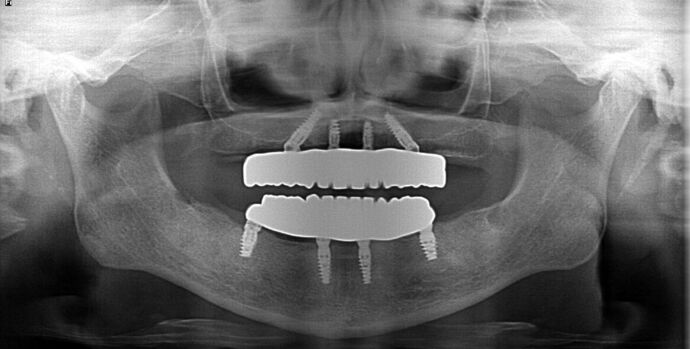

All-on-4/ Full Mouth Dental Implants / Teeth in a Day: Case 20-Gummy smile and failing teeth treatment with Upper and Lower All-on-4 Bridges

This high school teacher was embarrassed about losing her teeth one at a time and had multiple infected teeth causing her pain. She was also unhappy with her gummy smile and found Dr Bidra online. She was informed by 2 other dentists that her gummy smile could not be corrected by dental implants. Dr. Bidra was able to successfully accomplish all her treatment goals by extracting all her teeth and installing Upper and Lower All on 4 implant bridges

Procedures : extractions, gummy smile, new implants, All on 4 , Teeth in a day, no bone grafting and full mouth reconstruction with monolithic zirconia bridges.

Testimonial : " I had a full mouth reconstruction including dental implants. I am so glad I found the solutions that I needed at a reasonable cost and done correctly. Had been thinking about it for a few years. Now , I am able to smile again. Dr. Bidra does amazing work. He is a friendly and professional man. His staff is very welcoming and on the ball”